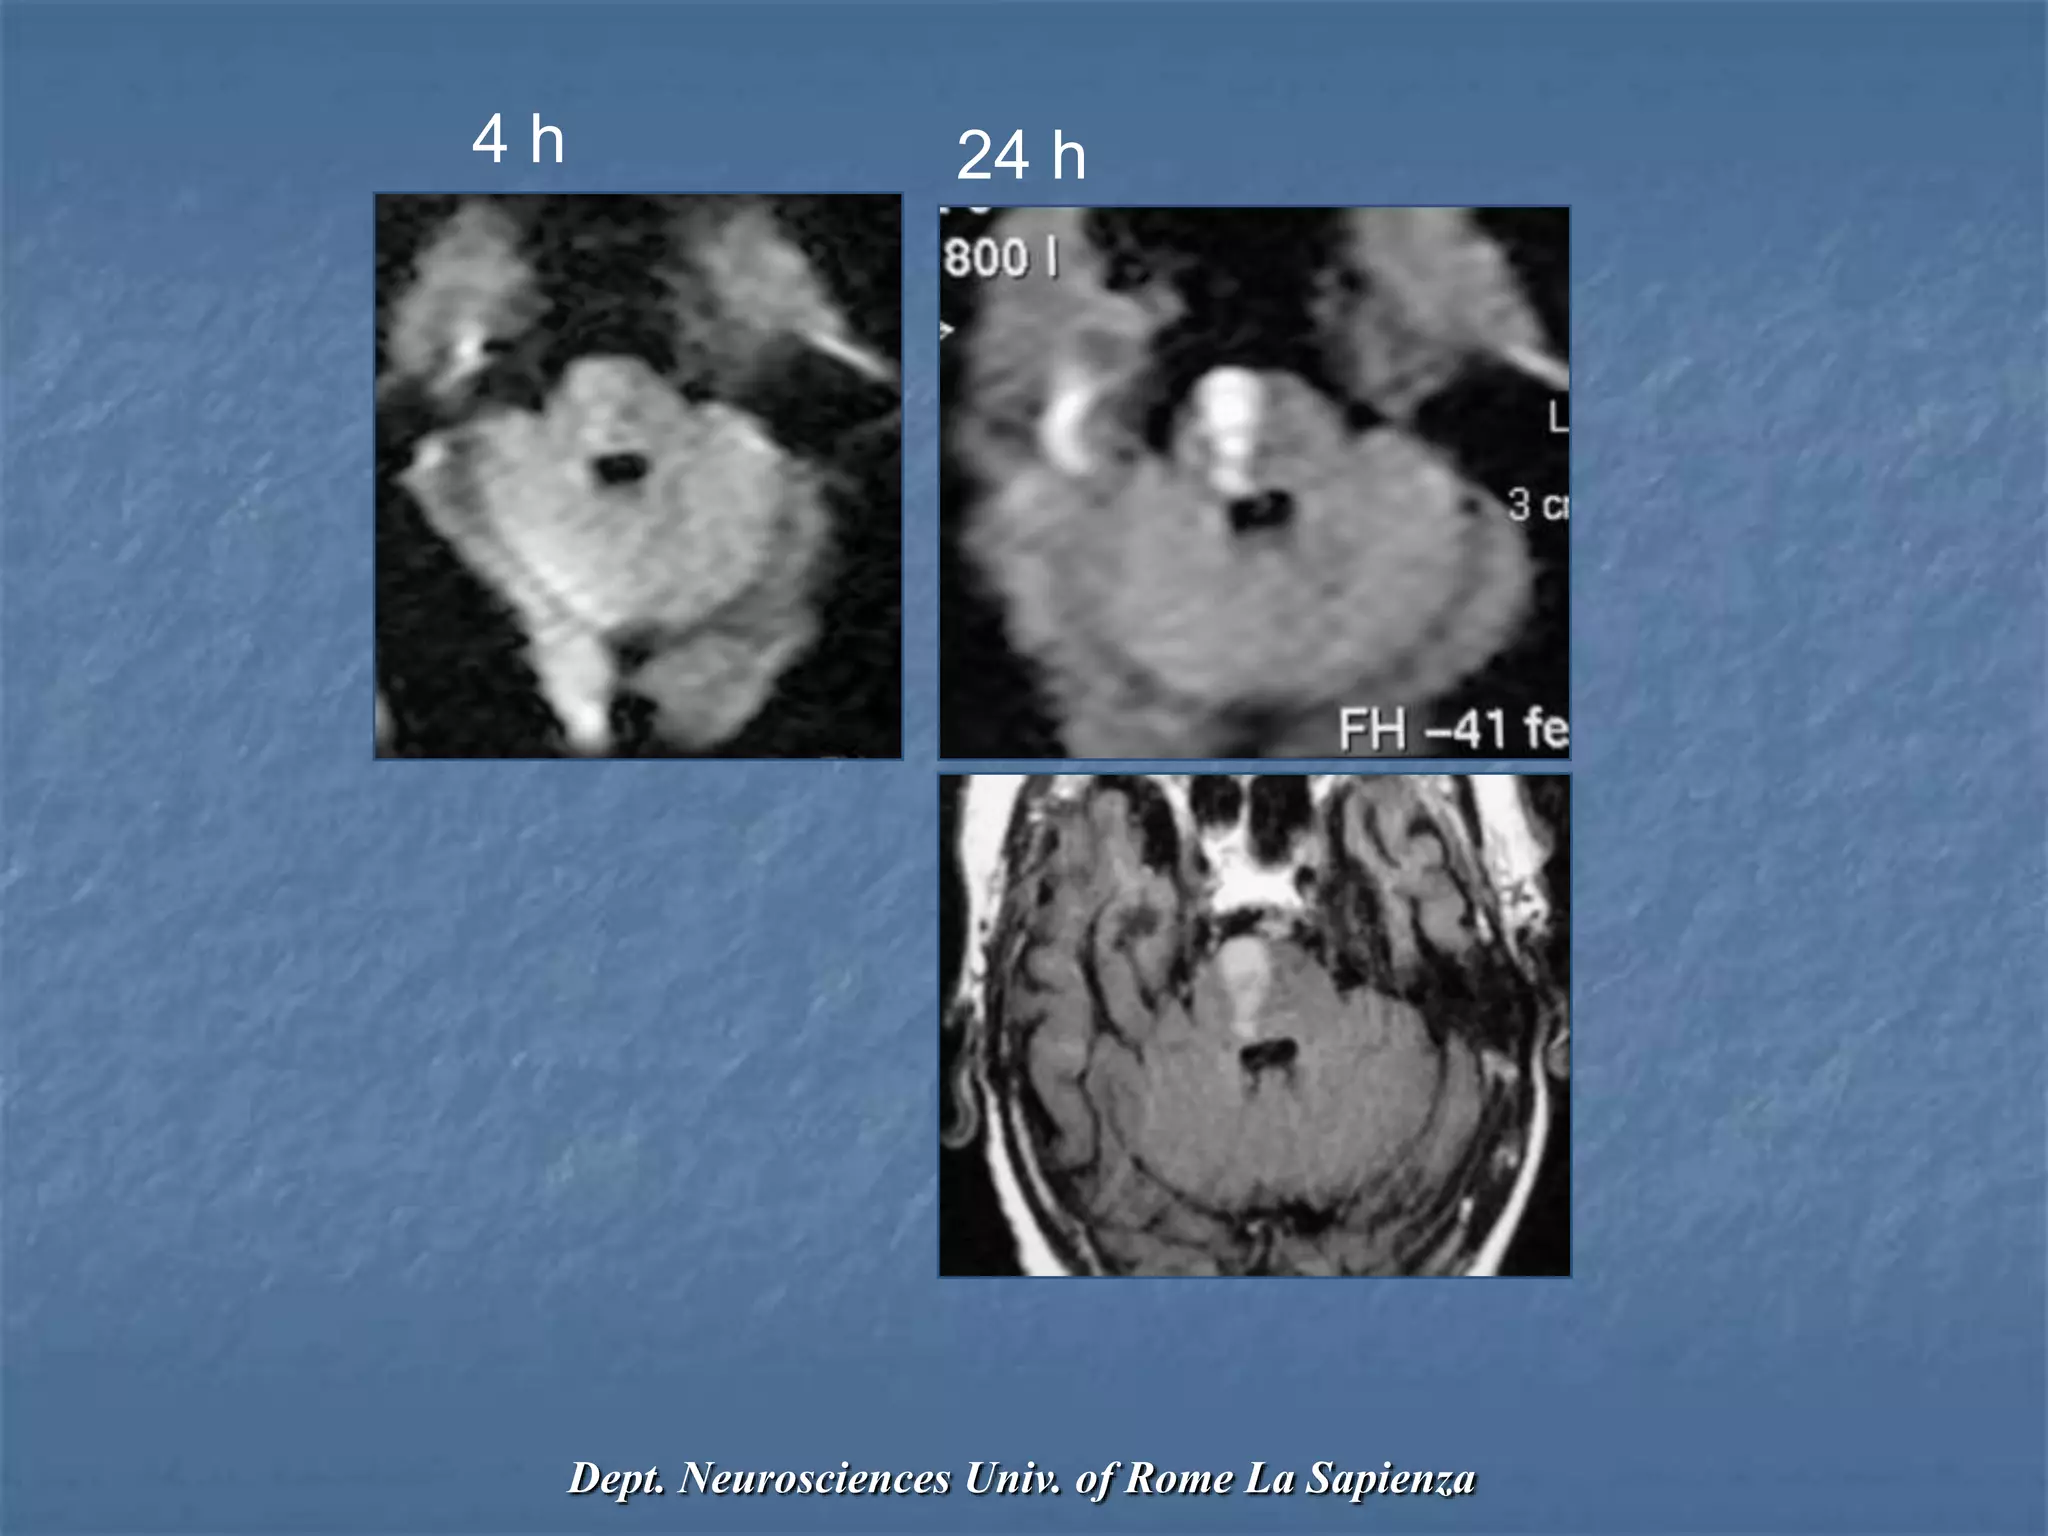

False Negative DWI

Brainstem infarct

Deep GM nucleus infarct

Neuroradiology2000;42:444–447

Stroke2000;31:1965–1972

AJNR 1999;20:1871–1875

Neurology 1999;52:1784-52

4 h 24 h

Dept. Neurosciences Univ. of Rome La Sapienza

Reversibility of Ischemic lesions on

DWI

Occlusion of MCA 1 hour - DWI lesion  or resolution

Occlusion of MCA 2 hour - Lesion size same or 

Radiology 2000;217:331-345

Successful thrombolysis may revert DWI changes

Diffusion changes in TIAs

• 29% to 67% will show restricted diffusion

• May reverse or persist

• Perfusion deficits 

Stroke vs TIA

DWI lesions of TIA are less intense

Stroke 2004;35:1095

AJNR 2004;25:1645-52